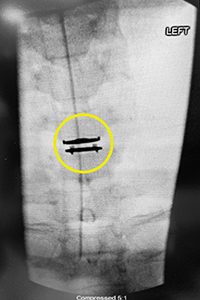

Cervical disc replacement interchanges the damaged disc with a new disc device, which allows for motion between the two vertebrae, avoiding the need for a fusion. The new generation implant, composed of two metallic endplate surfaces with polyethylene between, is attached to the upper and lower vertebra at the affected disc level. The disc replacement device is secured in place with an anchor to the bones. As a result, the implant can behave as a functioning joint with a normal range of motion.

Previously, surgeons used the cervical fusion technique to treat cervical disc disease. This procedure placed a plate with screws to the front of the spine to provide initial stability, which assisted in achieving a solid fusion. Following this fusion, patients were often immobilized for weeks.

Benefits of this new generation of cervical disc replacement compared to cervical fusion can include faster recovery, shorter hospital stays, smaller incisions with less scarring, implant longevity, and a quicker return to daily activities. Its new design without the screw fixation preserves and restores the neck’s range of motion.